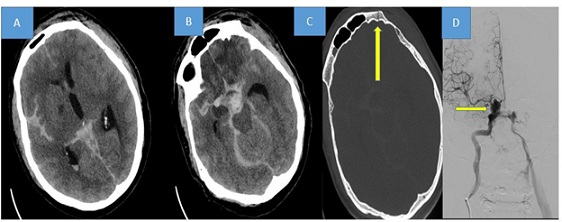

To initiate endovascular embolization, the balloon assistance technique was utilized. Although the initial placement of the coils proceeded without complications, a micro-coil spontaneously disconnected while delivering a 6-10mm x 30cm coil. Retrieving the disconnected coil mechanically posed a risk of compromising the previously inserted coil cast. To prevent the occurrence of ICA thrombosis or even potential late migration, the detached portion of the coil was straightened and elongated using a thrombectomy stent measuring 6x30mm. During this process, a complete closure of the carotid-cavernous fistula was observed in the subsequent DSA. The proximal part of the elongated coil was secured using self-expandable stents measuring 7 mm x 40 mm to maintain its straightened position. A final run DSA revealed a fixed coil firmly pressed against the carotid wall by the stent, confirming the complete closure of the carotid-cavernous fistula (Figure 2).

Figure 2: Image “A’’ showed the spontaneously disconnected coil in the right internal carotid artery. (Yellow arrow) The detached portion of the coil was straightened and elongated using a stent proximally and distally (yellow arrows, (B). A final run DSA revealed a fixed coil firmly pressed against the carotid wall by the stent, and complete closure of the carotid-cavernous fistula (C).